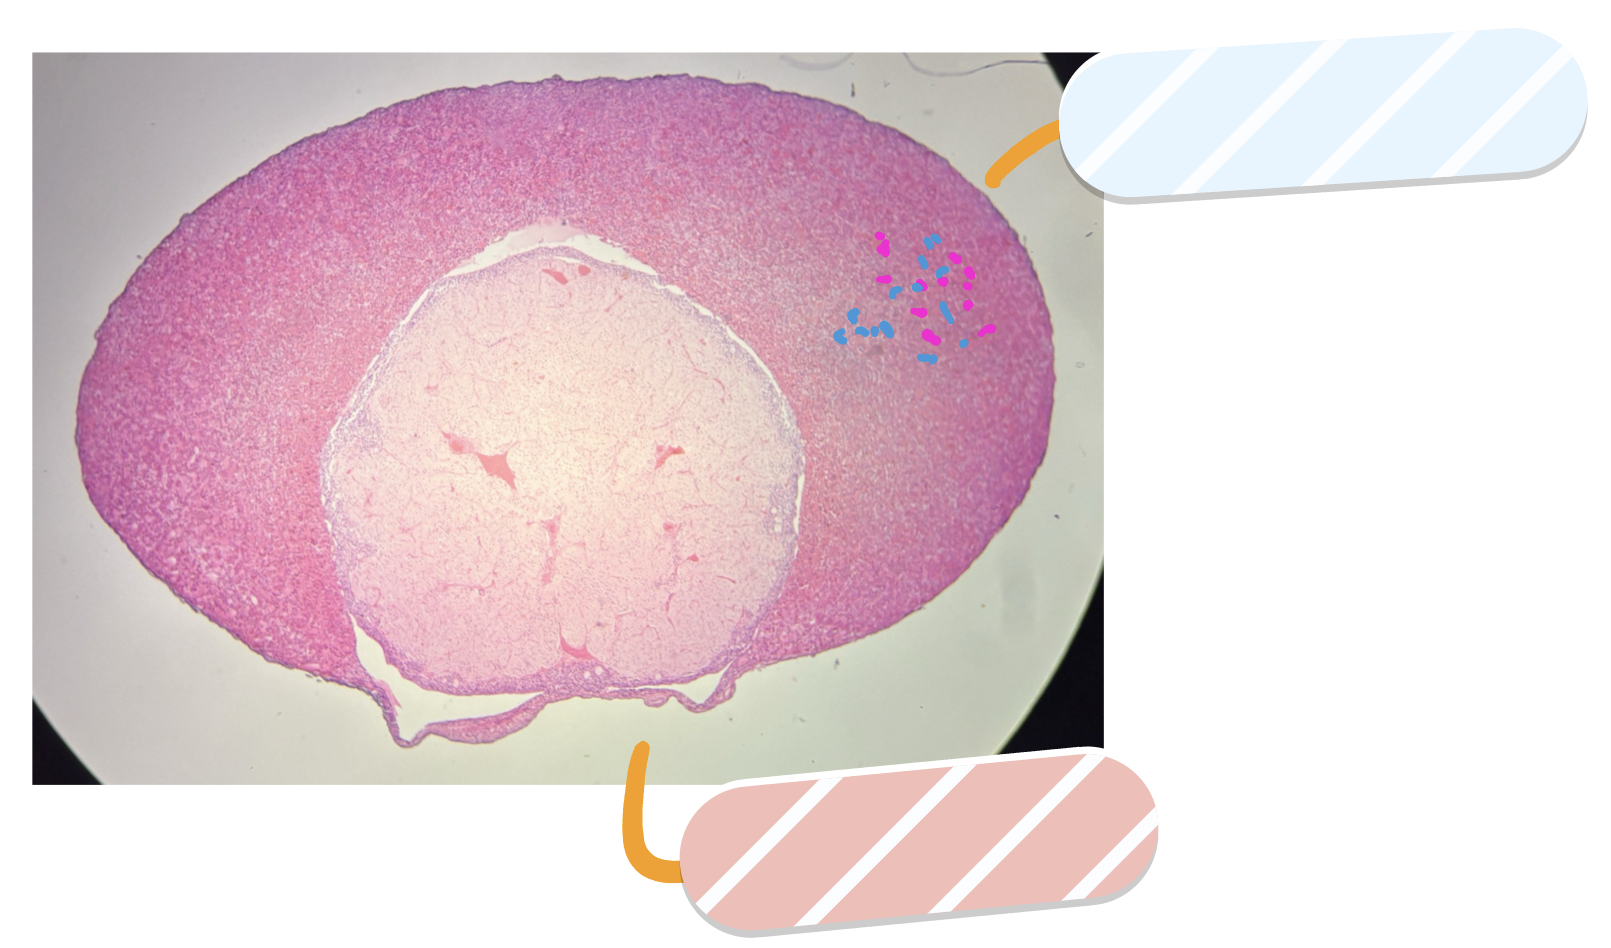

What is this a slide of?

Ovary

What is red?

Cortex

What is orange?

Corpus luteum

What is yellow?

Mature tertiary follicle

What is green?

Antrum

Primordial follicles

Corona radiata

What is cyan?

Oocyte